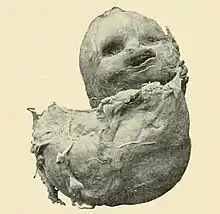

In 1880, German physician Friedrich Küchenmeister reviewed 47 cases of lithopedia from the medical literature and distinguished three subgroups: Lithokelyphos ("Stone Sheath"), where calcification occurs on the placental membrane and not the fetus; Lithotecnon ("Stone Child") or "true" lithopedion, where the fetus itself is calcified after entering the abdominal cavity, following the rupture of the placental and ovarian membranes; and Lithokelyphopedion ("Stone Sheath [and] Child"), where both fetus and sac are calcified. Lithopedia can originate both as tubal and ovarian pregnancies, although tubal pregnancy cases are more common.[2]

Lehmann, a widow from Olbersdorf, was diagnosed with lithopedion in 1823 by an obstetrician in Zittau, and treated by Küchenmeister before he moved to Dresden in 1859. Upon her death, Küchenmeister performed her autopsy and used her case to describe the lythokeliphos category.[7] |